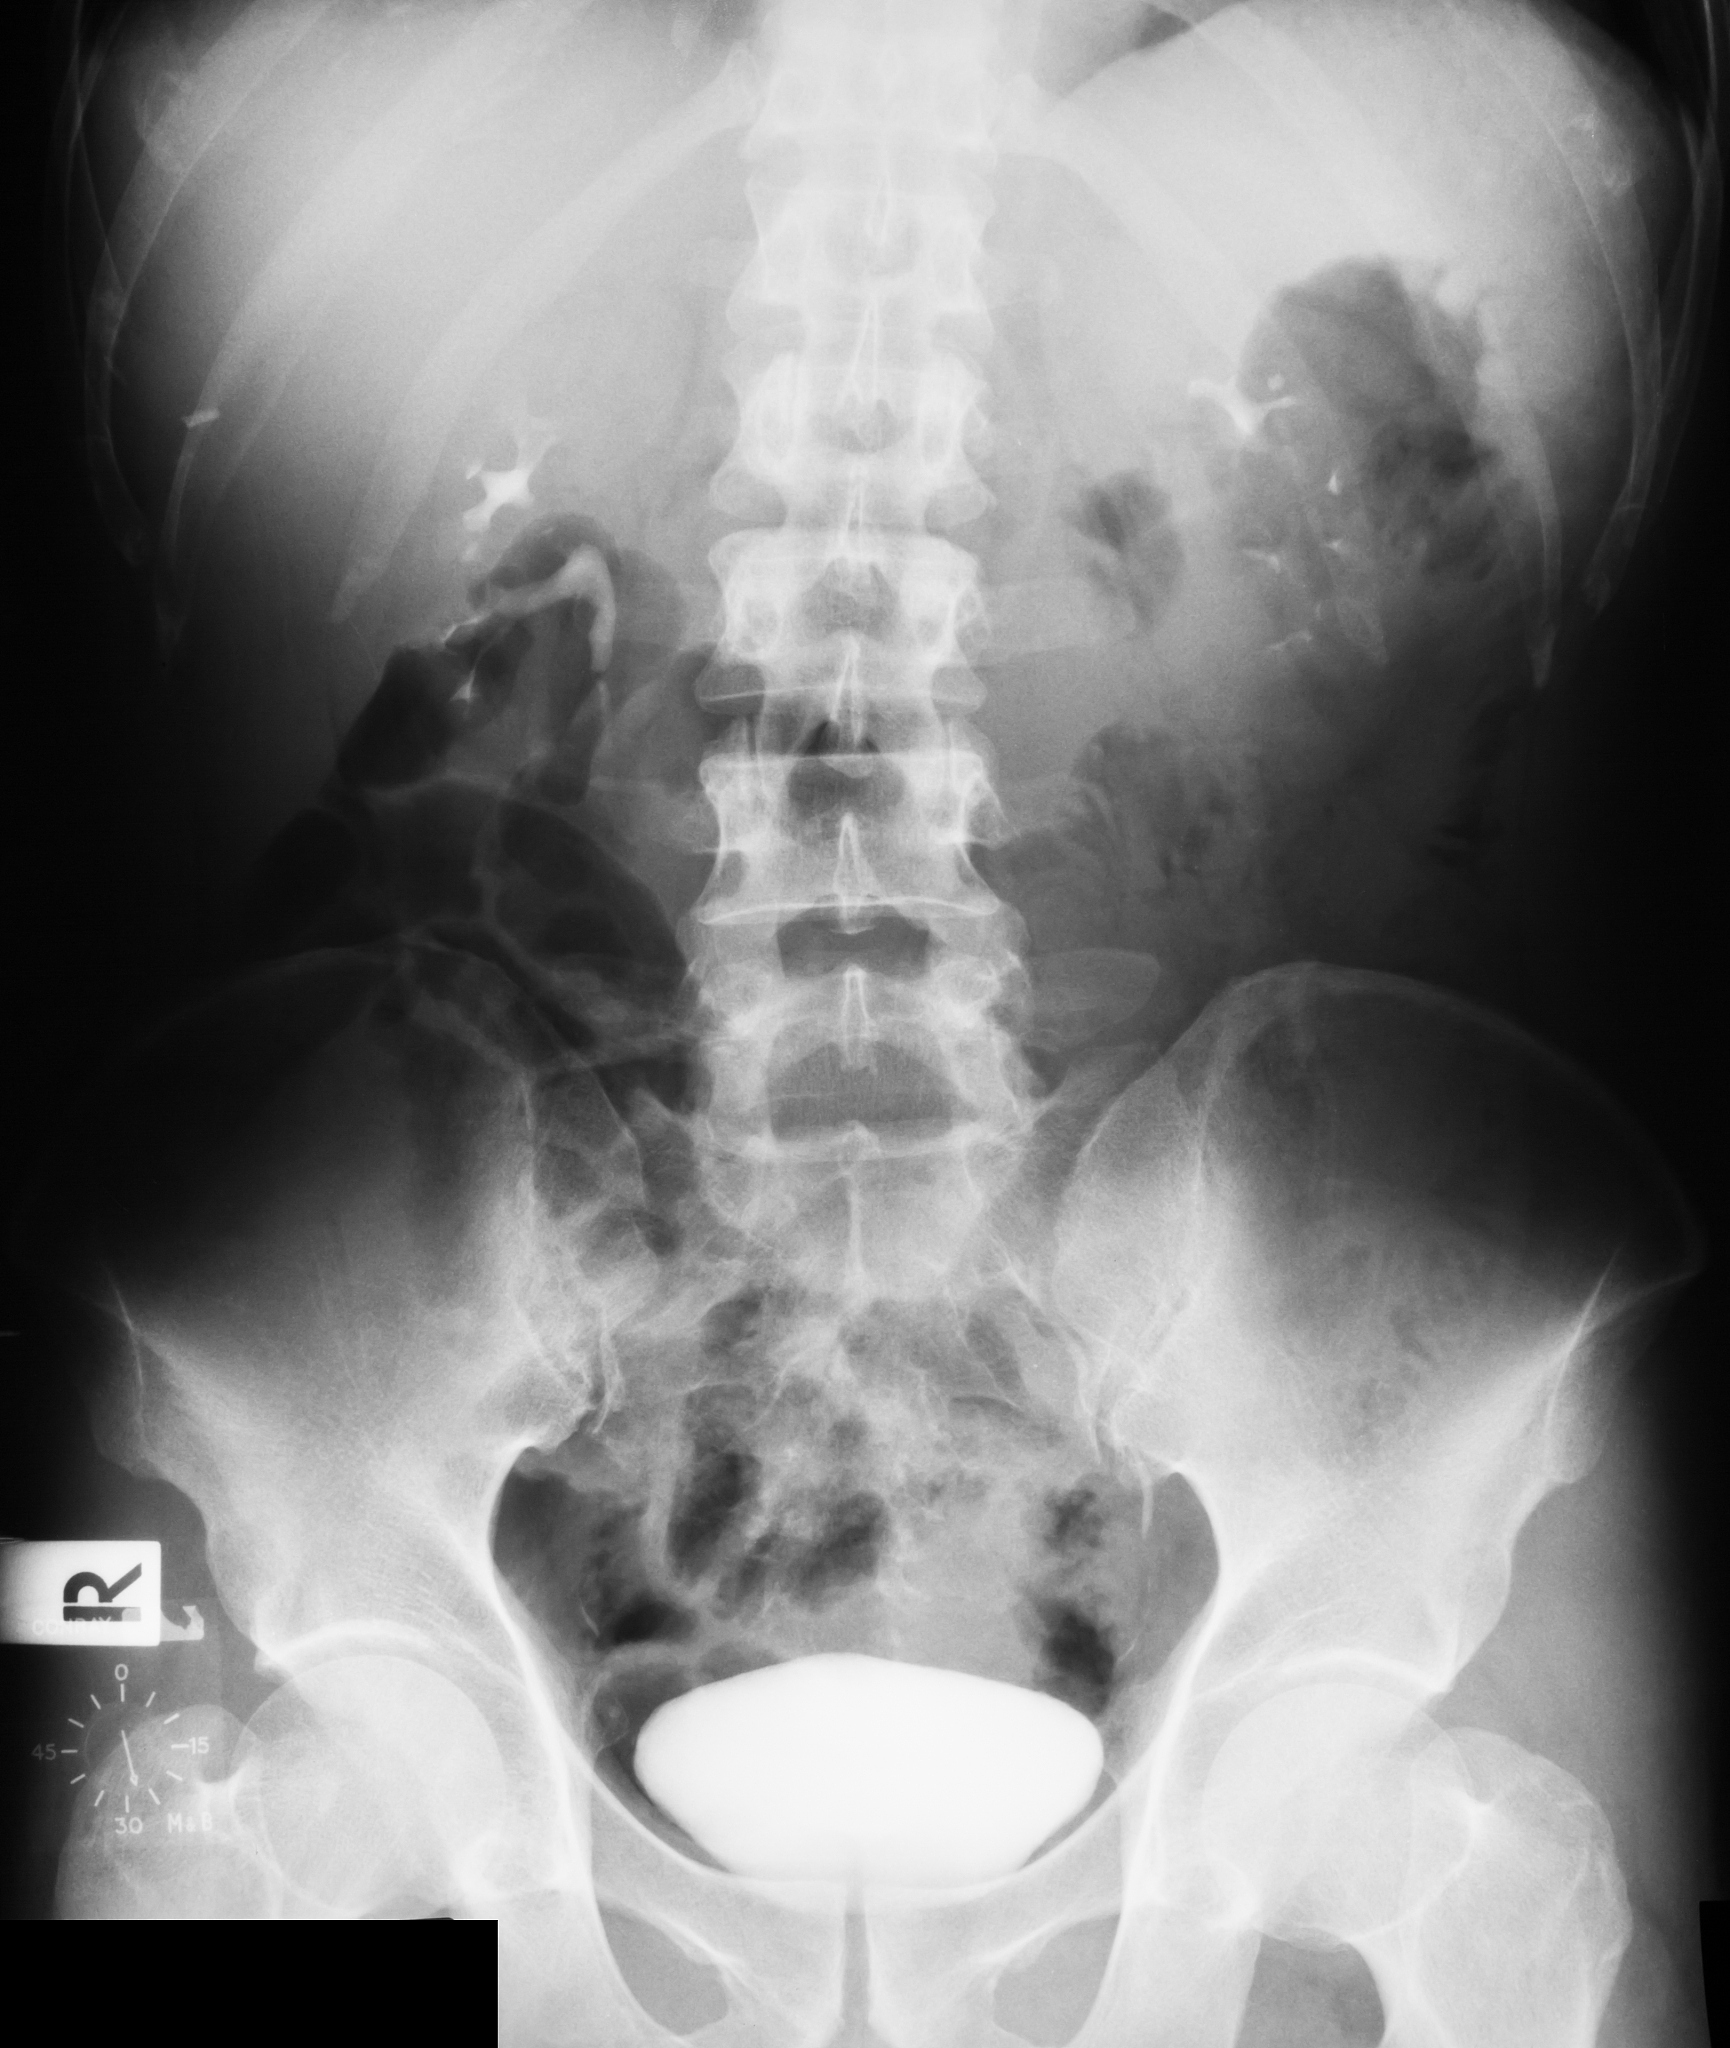

2.尿结石:尿结石是在尿液中形成的硬块,可以卡在尿道中,导致尿痛和尿流不畅。